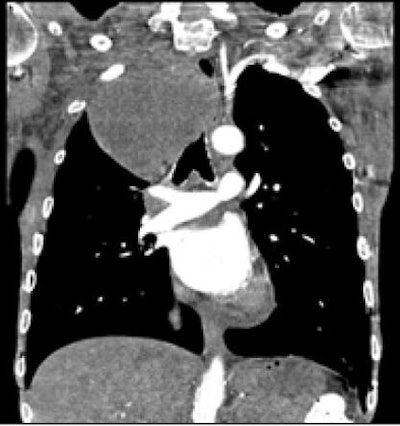

![]() |

| A 47-year-old patient presented with shortness of breath. Ultrafast pitch 3 coronary CTA revealed a large mass in the trachea. The quality of the image acquired in 2.71 seconds was rated as excellent. All images courtesy of Dr. Martine Rémy-Jardin, Ph.D. |